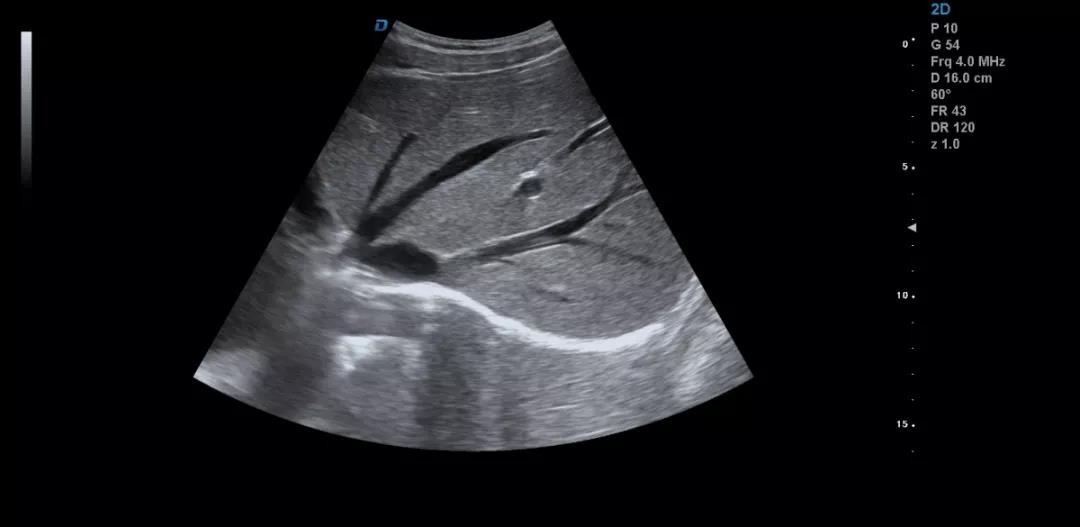

眾所周知,肝臟有很多檢查死角,成為超聲檢查的盲區(qū),如肺和骨所掩蓋處,肝右前上段及右后上段的膈頂部,左外葉外側角區(qū),沿肝臟表面的肋骨下區(qū)等等部位,只有極其細致的檢查配上精巧的手法才能盡可能的顯示清楚這些部位。

如果我們能夠細致的檢查每個病人,所謂的肝臟死角能夠盡可能的探測到,肝臟的死角其實只有膈頂部,其他的部位如果能細致檢查都可以探測到。

肝左葉掃查時,矚患者深吸氣,可以盡量使肝下移,更接近體表,顯示清楚,掃查至外側角肝臟消失的位置。然后探頭連續(xù)滑動,沿肋緣下斜切,矚患者深吸氣,探頭做扇形掃查,盡可能側動探頭至與皮膚平行,肝臟的絕大部分病變不會被遺漏。

對于肥胖體型或腹腔臟器明顯的,這種方法就不合適,可以采取肋間斜切的方法,自下而上逐個肋間連續(xù)掃查,注意不要做跳躍式掃查,這樣容易眼花也容易遺漏病變。

肝臟膈頂部掃查體會:

1)一般是讓患者深吸氣,讓肝臟下移,然后探頭盡量上翹;

2)當然很多患者因肥胖或肺氣的干擾會顯示更差,這時我就讓患者深呼氣,把氣全部吐干凈,然后屏氣掃查;

3)還有就是不要沿著肋間隙掃查,而是和肋間隙成一定的角度緩慢向右上方腋前線掃查;

4)在平臥位掃查時,在橫切腎臟時探頭盡量上翹,甚至與腹壁平行,當然在右側肋緣下也行;

5)變換體位掃查,肝臟因重力作用產生移位。左側臥位、右側臥位、各種斜位、還有站立位等等。

掃查肝臟時要配合患者的呼吸運動,采取你動我靜,你靜我動的掃查方法,并最大限度的側動探頭,最大角度的顯示肝臟。

發(fā)現肝臟病變時要多切面多角度掃查,可以了解病變的解剖位置并排除假陽性。